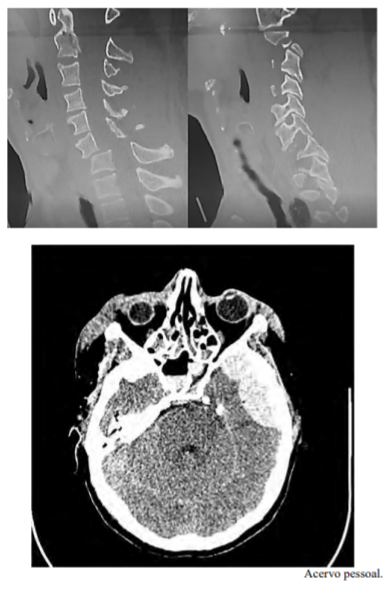

Uma paciente de 27 anos de idade, com 63 kg, previamente hígida, é levada ao hospital pelos bombeiros, em imobilização padrão, após colisão do próprio carro em uma árvore. Queixa-se de cefaleia, cervicalgia e desconforto em ombros/membros superiores. Ao exame inicial, constatam-se AC = RC2T com BNF; FC = 110 bpm; AP = MVF sem RA; FR = 18 irpm; PA = 140 mmHg x 90 mmHg; e SatO2 = 99%. Na avaliação inicial, apresenta abertura ocular espontânea, pupilas isofotorreagentes, com colar cervical, fala confusa, amnésia lacunar e dor à palpação da coluna cervical, obedecendo a comandos, porém com dificuldade de mobilizar braços (força distal 1 e força proximal 4, em ombro e braço direito, e grau 3 à esquerda), com força aparentemente preservada em pernas. É realizada a tomografia computadorizada (TC) de crânio e coluna cervical, segundo as imagens apresentadas.

Após redução facetária e (ou) fixação 360°, espera-se que a paciente tenha alívio parcial da cervicobraquialgia, porém sem apresentar melhora motora, já que o deficit neurológico já está estabelecido.